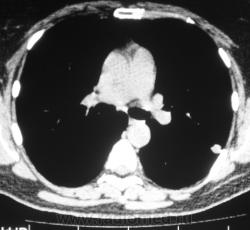

Произведена КТ.

КТ хотелось бы посмотреть в dicom-формате, меняя режимы, но на мой взгляд образование содержит известковые включения. Хотя, я не настаиваю, дождемся мнения коллег.

Нет "волшебных методов", можна поставить диф. ряд. Я бы дала такое заключение: хондрогамартрома, дифференцировать с туберкуломой, периферический рак менее вероятен. Можно жизнь прожить с гамартромой, а может озлиться в саркому. На практике был случай, когда лет 10 наблюдалась классическая скиалогически туберкулома, которая за полгода выросла и оказалась аденокарциномой. Таким образом, при любом раскладе, хирургическое лечение не является ошибкой, но решение об операции на легком должен принимать консилиум.

Дело не в желании, а в смысле. Что тут ещё можно сказать? На мой взгляд-мелкая, частично кальцинированная туберкулома.

Да, более туберкулёма.